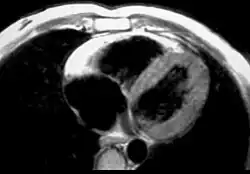

Magnetic resonance imaging

Fatty infiltration of the RV free wall can be visible on cardiac MRI. Fat has increased intensity in T1-weighted images. However, it may be difficult to differentiate intramyocardial fat and the epicardial fat that is commonly seen adjacent to the normal heart. Also, the sub-tricuspid region may be difficult to distinguish from the atrioventricular sulcus, which is rich in fat.

Cardiac MRI can visualize the extreme thinning and akinesis of the RV free wall. However, the normal RV free wall may be about 3 mm thick, making the test less sensitive.